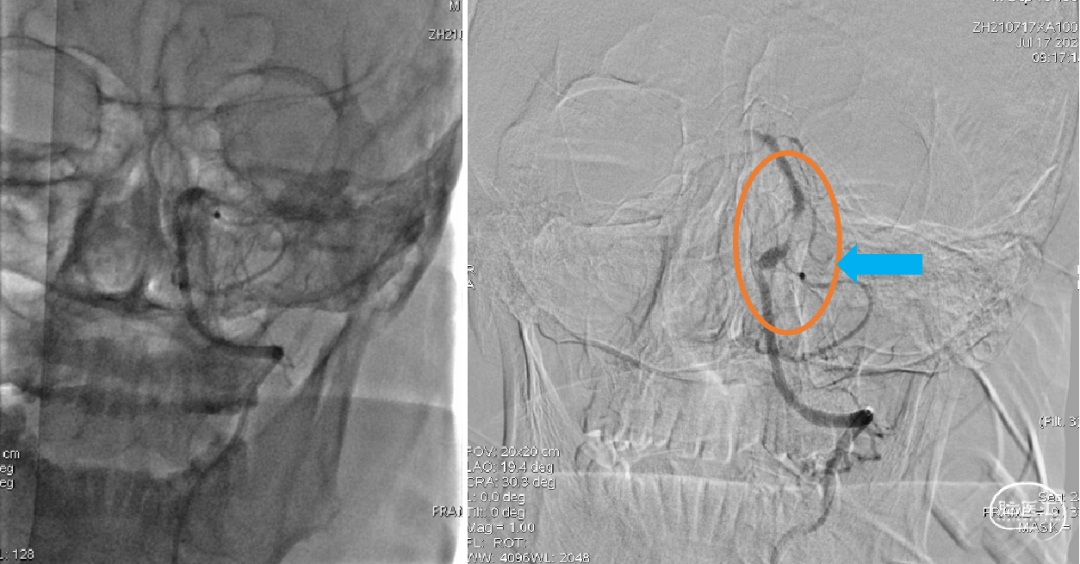

1、术后即刻造影;2、15分钟后再次造影,基底动脉近端仍有重度狭窄,远端血流稀疏、缓慢。

1、选择2×15mm球囊针对狭窄处进行亚满意扩张;2、术后造影,狭窄好转,远端血流明显改善,观察15分钟后未见明显变化后结束手术。